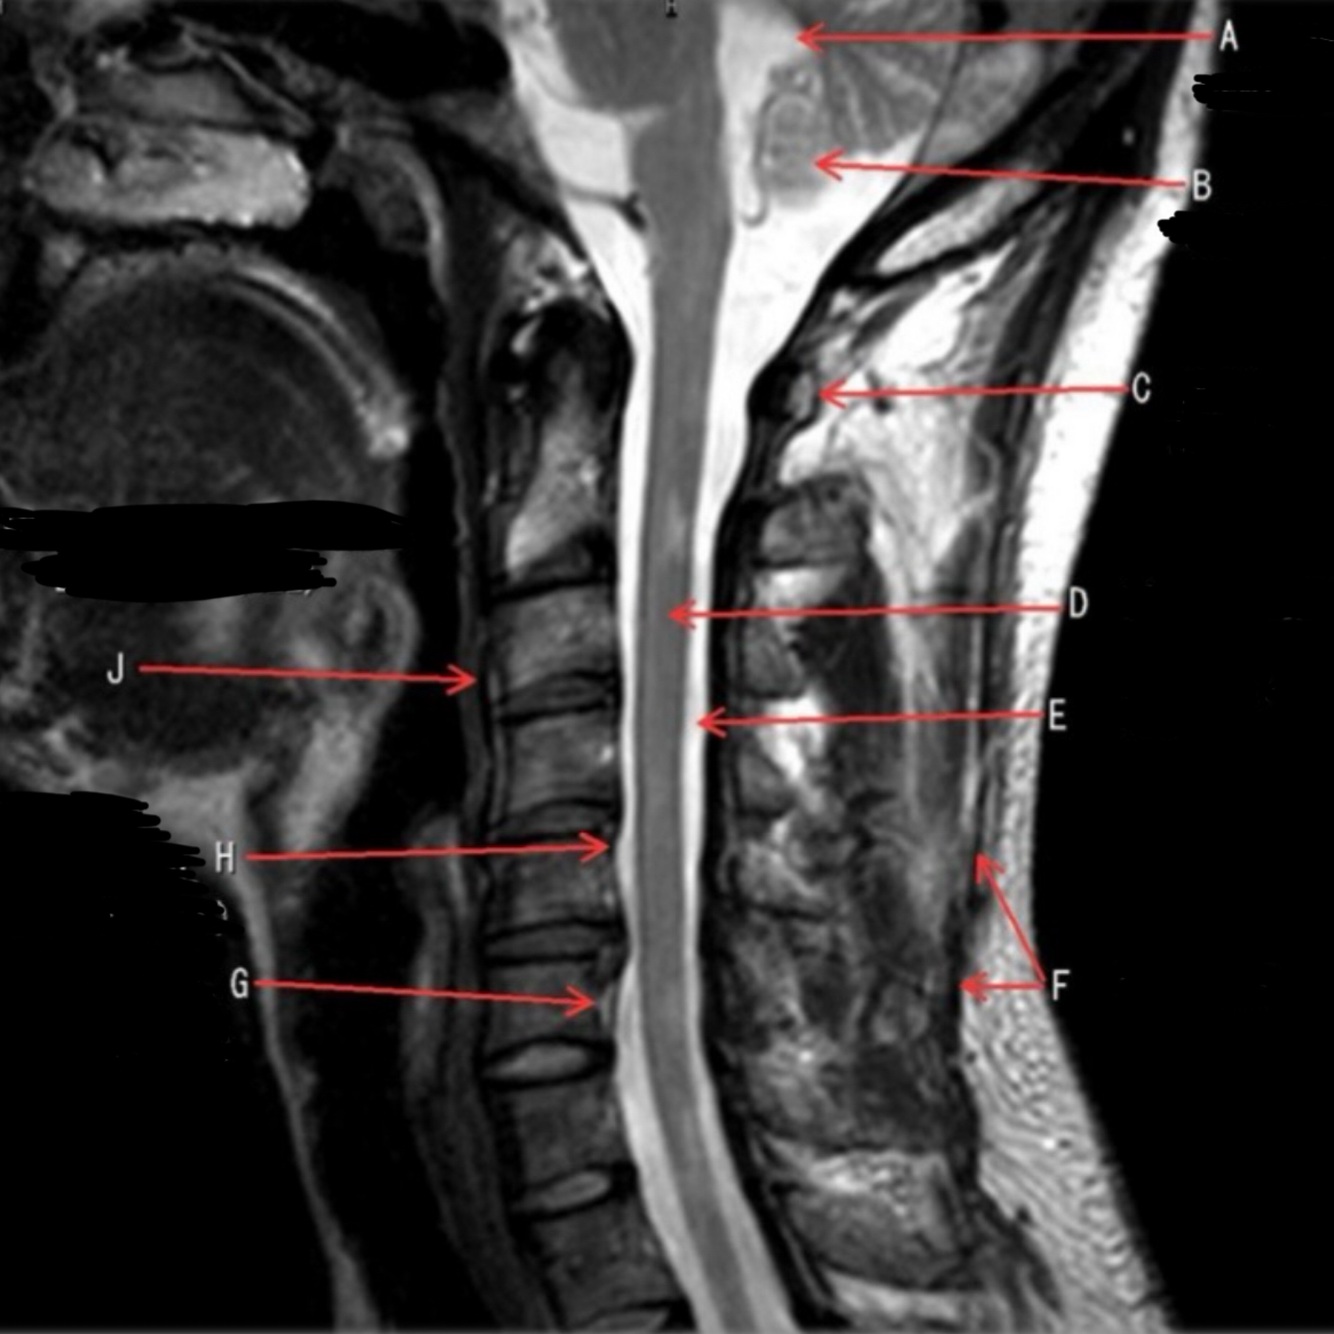

1

What is letter A?

4TH VENTRICLE

What is letter B?

CEREBELLUM

Q

A

4

What is letter D?

5

What is letter E?

6

What is letter F?

SPINOUS LIGAMENT

7

What is letter G?

VENUS PLEXUS

8

What is letter H?

POSTERIOR LONGITUDINAL LIGAMENT (PLL)

9

What is letter J?

ANTERIOR LONGITUDINAL LIGAMENT (ALL)